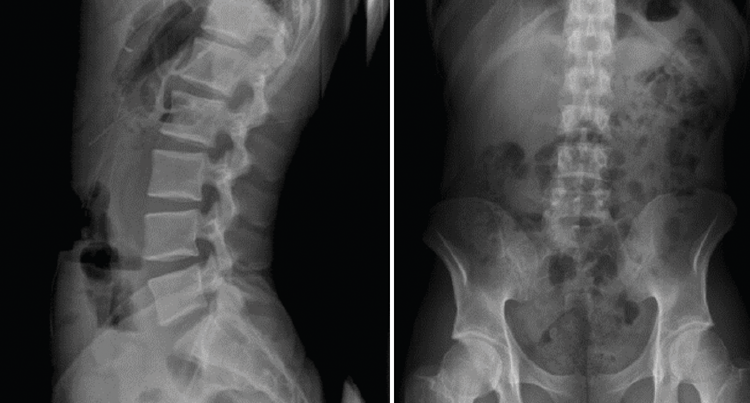

Proyecciones radiológicas

La más frecuentemente utilizadas son la proyección AP y L. Se debe procurar incluir al menos hasta T11 y el borde superior de las caderas (Figura 8).

Figura 8. Radiografía anteroposterior lateral y lumbar.

Las radiografías oblicuas no son necesarias de forma rutinaria, estando indicadas en pacientes con una elevada sospecha de presentar una espondilólisis (Figura 9).

Figura 9. Radiografías oblicuas de columna.